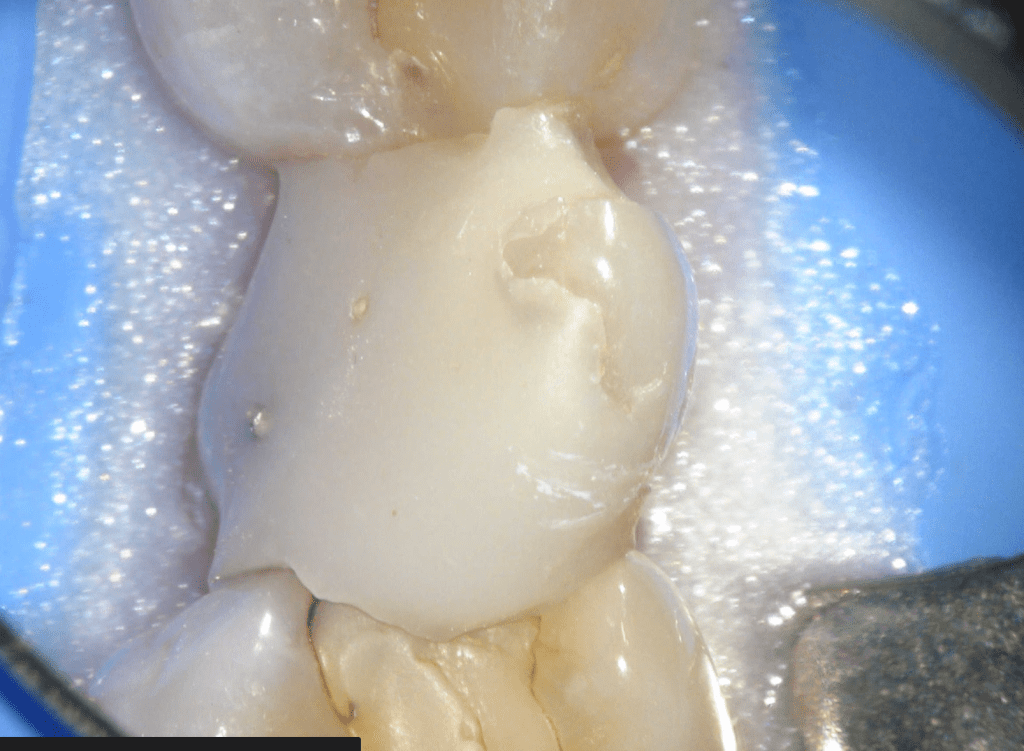

Reconstrucción preendodóntica

Molar superior

Reco preendo + 4 conductos molar superior

Reco preendo, 2o Molar superior